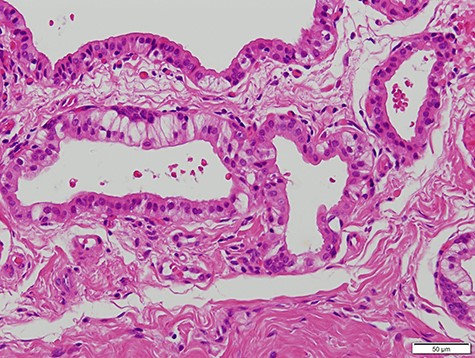

A 63-year-old man was referred to our hospital for treatment of a nodule on his tongue in May 2003. His medical history included Wolff–Parkinson–White syndrome and atrial fibrillation, both of which were controlled adequately by his primary care physician. Physical examination revealed very slight swelling at the right edge of his tongue. The patient reported some spontaneous pain. It was diagnosed as inflammation of the foliate papilla; the patient was followed-up with a gargle prescription. In September 2005, an elastic soft mass, 4 mm in diameter, was observed along the right edge of his tongue (Fig. 1). It was clinically diagnosed as a benign tumour and removed under local anaesthesia. Microscopically, the lesion was composed of multiple cysts of various sizes and shapes, with or without papillary intraluminal short projections (Fig. 2). Many cyst cavities contained eosinophilic fluid. The lesion was well-delineated, but the capsular structure was ill-defined. The stroma was fibrous connective tissue without lymphocytic components. The cystic cavities were lined by a bilayered epithelium composed of luminal columnar cells and basal cuboidal cells. Both luminal and basal epithelial cells were eosinophilic; some clear cells were seen (Fig. 3). Mitotic figures and cellular atypia of epithelial cells were not seen. Immunohistochemically, both luminal and basal cells were CAM5.2+, basal cells were p63+, apical half of the luminal cells were 34βE12+, and the liminal surface was CEA+. The specimen was diagnosed as cystadenoma, based on the histopathological findings.

Micrograph showing the lesion composed of multiple cysts of various sizes and shapes (haematoxylin–eosin stain, 100×).